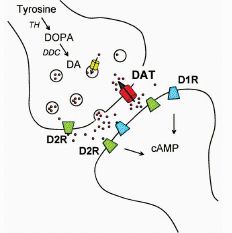

Dopamin, seine D1-, D2-, D3-, D4-, D5-Rezeptoren, beschwichtigend wirkenden D2-,

D3–Autorezeptoren, sein Wiederaufnahme-Transporter DAT und

Abbau-Enzyme COMT und MAO A spielen dabei eine ausschlaggebende Hauptrolle.

untrennbar eng miteinander verbunden. Die folgenden zwei Grafiken zeigen im Überblick neuro- und molekularbiologische Lebensprozesse im Dopaminsystem: